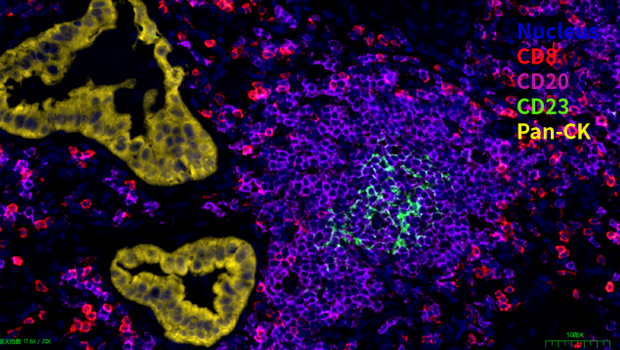

Nucleus,CD8, CD20, CD23, Pan-CK